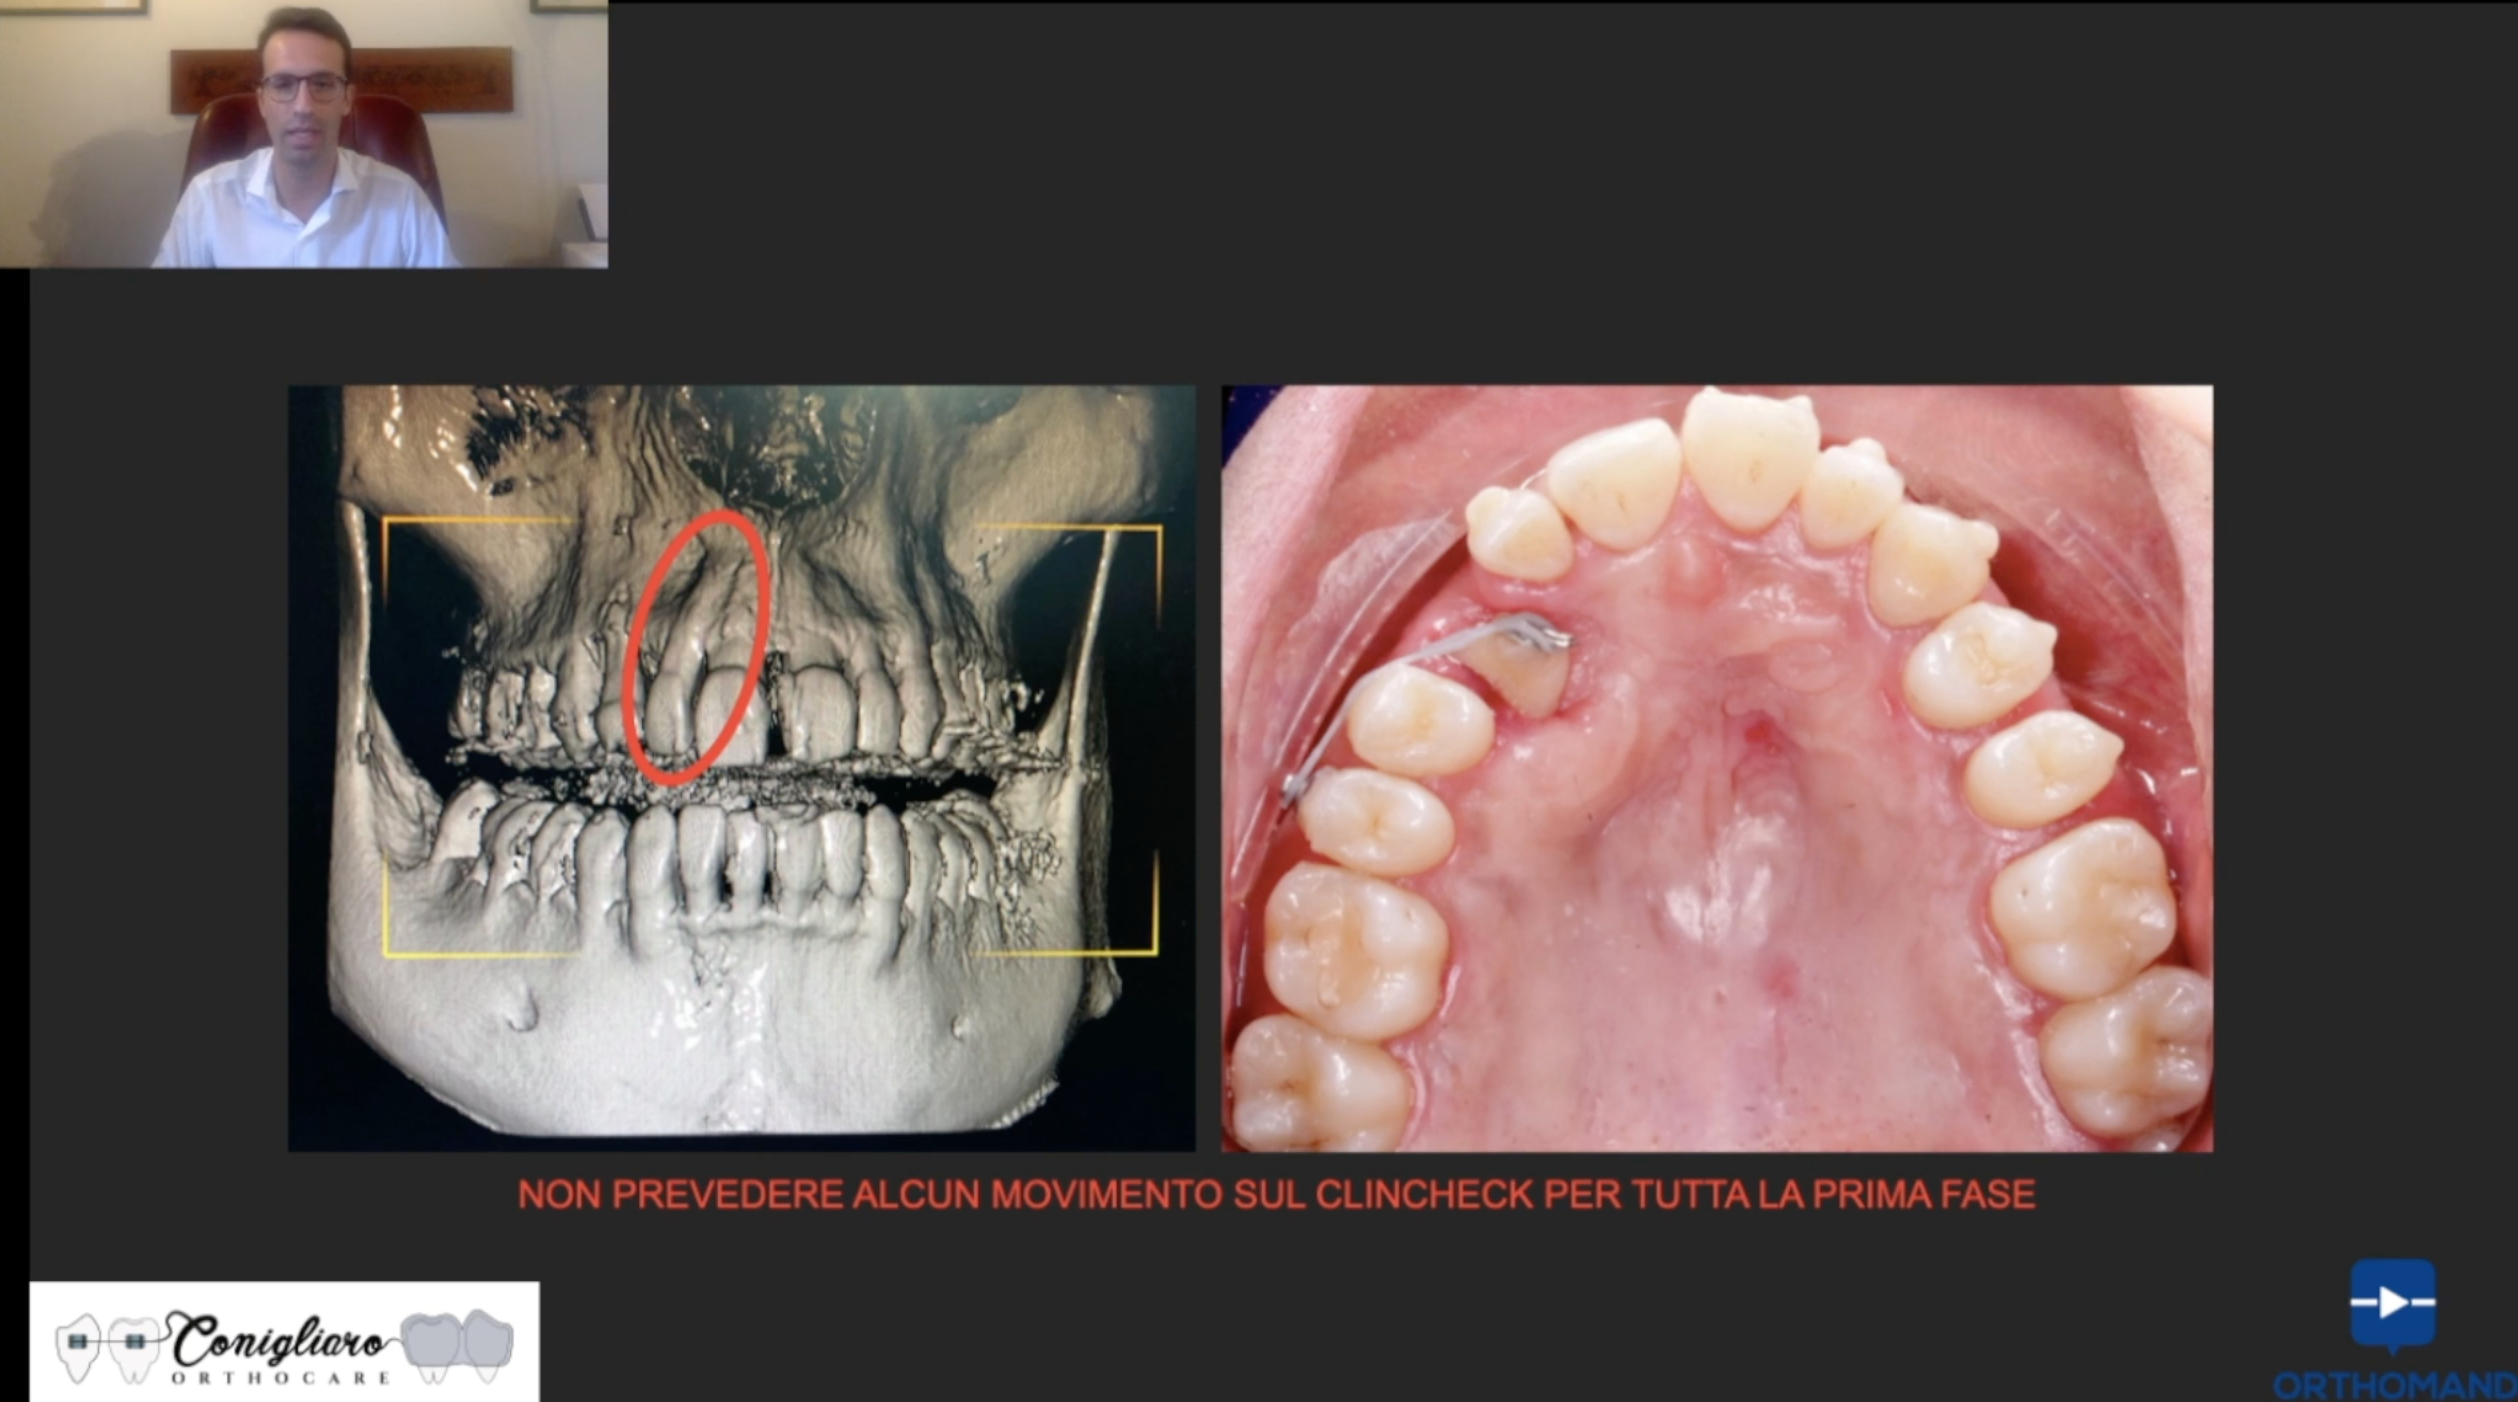

I canini inclusi sono da sempre un’importante sfida per l’ortodontista. La gestione di questi con allineatori è una novità assoluta, che può trovare ampio spazio nella pratica clinica quotidiana. Con una corretta pianificazione e gestione della biomeccanica, riusciremo a trattare anche i casi più complessi

- La biomeccanica da applicare e l’integrazione di questa con il Clincheck

- Tipologie di trazione del canino incluso con allineatori